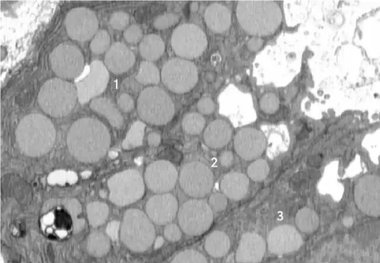

سلول‌ها برای جوان شدن «استفراغ» می‌کنند!

یک مطالعه جدید نشان می‌دهد که سلول‌ها برای التیام و جوان شدن دوباره، مواد زائد درون خود را استفراغ می‌کنند.